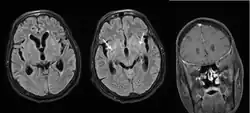

Disseminated cryptococcal meningitis

Cryptococcal meningitis (infection of the meninges, the tissue covering the brain) is believed to result from dissemination of the fungus from either an observed or unappreciated pulmonary infection. Often there is also silent dissemination throughout the brain when meningitis is present. People with defects in their cell-mediated immunity, for example, people with AIDS, are especially susceptible to disseminated cryptococcosis. Cryptococcosis is often fatal, even if treated. It is estimated that the three-month case-fatality rate is 9% in high-income regions, 55% in low/middle-income regions, and 70% in sub-Saharan Africa. As of 2009 there were globally approximately 958,000 annual cases and 625,000 deaths within three months after infection.[27]